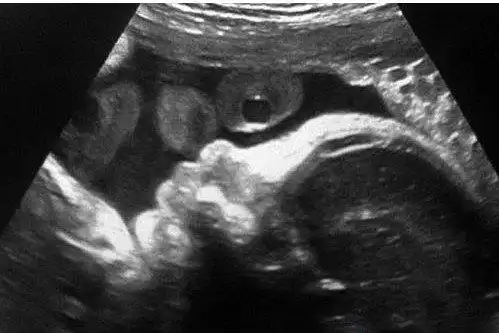

6月17日下午,欧弟通过微博发出了妻子的b超照,宝宝的样态已清晰可见